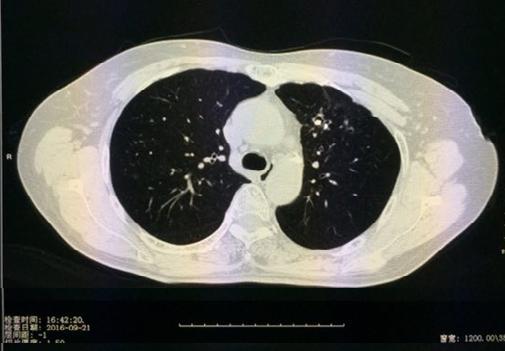

肺部结节是指≤3cm的肺部圆形病变,无卫星灶、无淋巴结及远处播散。肺部小结节是指≤1cm的结节,又称亚厘米结节。还有一个经常在肺部CT检查影像报告上看到的术语GGO,它是指肺部磨玻璃结节,是一种特殊类型的肺部结节,表现为密度轻度增高的云露状淡薄影/圆形结节,样子像磨砂玻璃一样,所以叫磨玻璃影。研究表明,18%-63%的毛玻璃样小结节是早期肺癌;肺部结节可以是弥漫性散生长,也可以仅聚集在局部。一般而言,弥漫性生长的结节良性病变的可能性大,局灶性生长的容易是肺部肿瘤。

西安交通大学附属胸科医院(西安市胸科医院)呼吸与危重症医学科设立 “肺结节一站式“综合门诊,构建并优化了肺结节/肺癌精准诊治体系,为就诊患者提供“一站式”服务:网上预约挂号-影像学检查-三维重建数字肺分析-必要时气管镜/内科胸腔镜检查-制定治疗建议-随访;同时,对于疑难肺结节患者,将由呼吸与危重症医学科、胸外科、肿瘤科等多学科专家共同商讨和制定个性化治疗方案,提高肺结节诊断的准确率,真正实现“病人不乱跑、医生围着病人转”的一站式服务。

病例1: 巩先生,体检发现左肺毛玻璃小结节,用EBUS-GS超声支气管镜进行检查,病理结果:隐球菌感染。